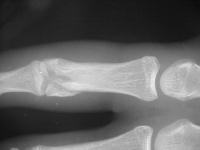

Unicondylar fractures of the phalangeal head are common, frequently unstable and unacceptably displaced. Although some may be treated successfully with percutaneous reduction and fixation, many require open reduction. In these cases, the screws were put right through the collateral ligament and sunk into the cortex. I think the simplest way to do this is to reduce and stabilize with two K wires, then remove the wires and replace with screws, one at a time, so reduction is maintained throughout. 1mm=39/1000" Kwire, so doing the math, here is how you choose the right sized Kwire to use as both drill and provisional fixation:

And another patient.